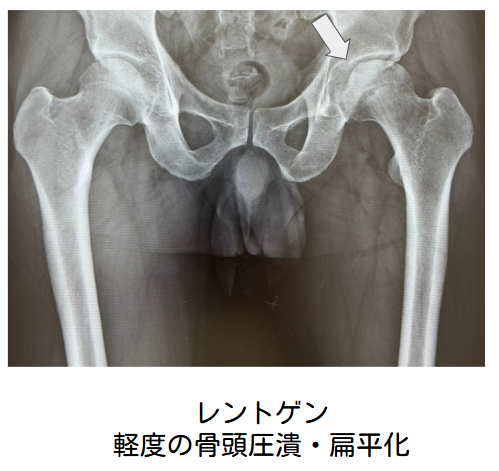

単純X線像では、壊死領域の周囲に帯状硬化像を認めます。また、骨頭の圧潰が生じると、関節面の不整像や軟骨下骨の骨折線(crescent sign)を認めます。

治療方針を決定するためには、病型(Type)および病期(Stage)分類を行う必要があります。病型は壊死範囲の局在によって分類され、単純X線像とMRIの両方またはいずれかで判定します。病期は大腿骨頭の圧潰と関節症性変化の有無について、骨頭の正面と側面の2方向X線像で評価を行います。